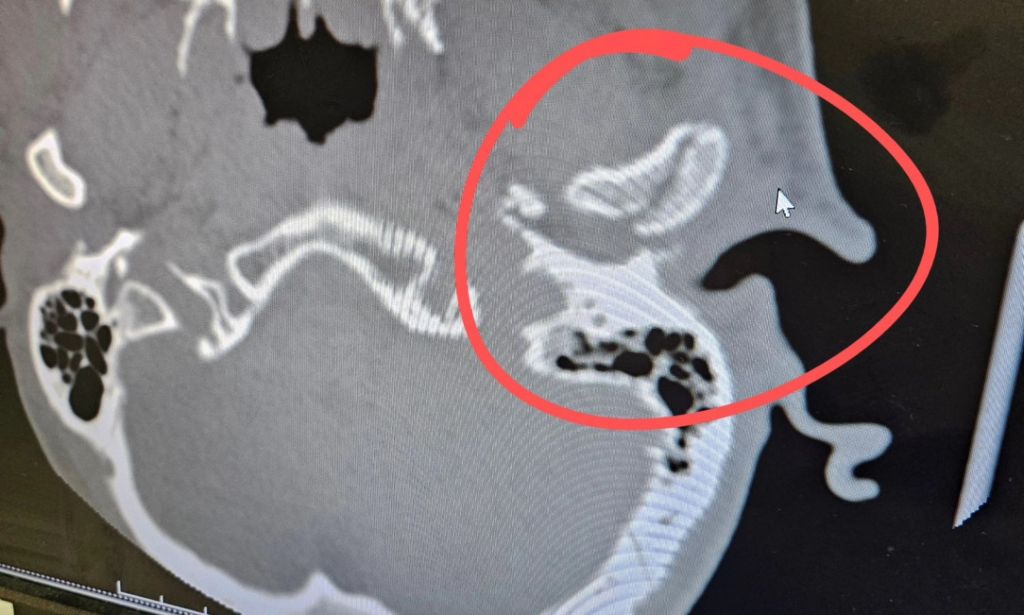

L'ouvrier du bâtiment a été emmené au centre médical Dell Seton où des tomodensitogrammes ont révélé qu'il avait la mâchoire cassée et une commotion cérébrale. Les médecins légistes ont trouvé un fragment de sa mâchoire dans son conduit auditif, qui était plein de sang.